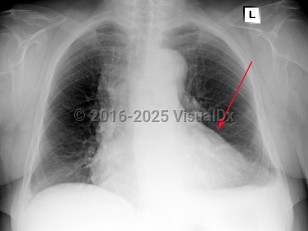

Pneumothorax

Spontaneous pneumothoraxSpontaneous pneumothorax

Tension pneumothorax